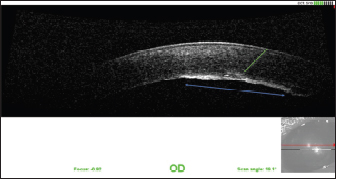

The AC was stabilized by intracameral injection of a viscoelastic gel (hyaluronic acid 1.6%, Ophteis Bio) by a perforating keratotomy port at 12 o’clock. As the base of the claw was crenelated, it was not possible to remove it through the site of penetration, which is why another perforating keratotomy port was made at 10 o’clock. The claw was grasped with Bonn’s pliers and then gently removed. The entry point of the claw and the 10 o’clock port were sutured by single stitches using polyglactin 9/0 (Vicryl 9/0). The pupil was then dilated by injection of 1 ml of epinephrine at a concentration of 1 mg/ml into the AC. The anterior lens was ruptured, and a heterogeneous traumatic cataract had already developed (Fig. 2). The lens was, therefore, removed by phacoemulsification via the port at 12 o’clock. After removal of the masses by irrigation/aspiration, the tear of the anterior capsule was shaped before injection of an implant (PFI 4X, Medicontur). The keratotomy port at 12 o’clock was sutured by three single stitches with Vicryl 9/0 after the removal of residual viscoelastic material by suction irrigation. At this stage of the surgery, a tear of the endothelium and Descemet membrane was visible, following the most likely trajectory of the claw into the AC (Fig. 3). Water bubbles were already forming in the corneal stroma. An injection of 0.25 μg of tissue plasminogen activator (Actilyse®, BOEHRINGER INGELHEIM) was performed in the AC at the end of the intervention to limit postoperative fibrinous collection. The claw was sent to the laboratory for bacteriological analysis.

Fig. 9. OCT of the cornea 1 year after the surgery. Note the fibrous metaplasia of the endothelium (blue arrow) and probable duplication of the Descemet membrane (green arrow).